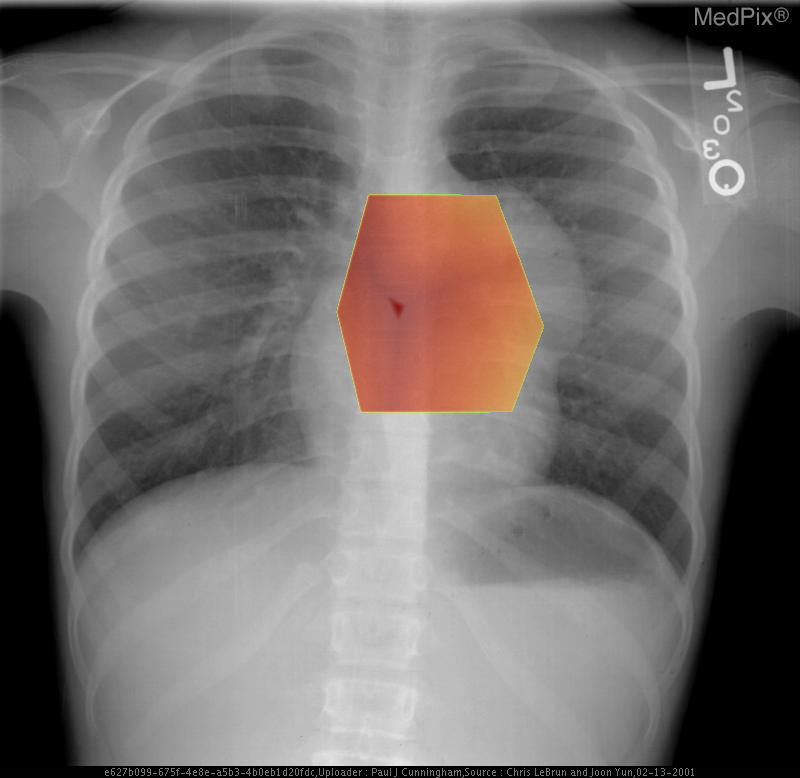

Mediastinal Teratoma

• Diagnosis: Mediastinal Mature Teratoma

1) Findings:

- Frontal chest radiograph, properly oriented: image-left = patient-right.

- Cardiac silhouette is mildly displaced toward the image-right (patient-left), suggesting mass effect from a mediastinal lesion.

- A well-circumscribed, rounded opacity occupies the image-left (patient-right) upper mediastinum, with smooth margins.

- The lesion shows heterogeneous internal density, including areas of relative lucency (suggesting fat) and opacity (possibly soft tissue or calcification).

- Lungs otherwise clear without focal consolidation or effusion.

- Bony thorax intact with no visible rib destruction or vertebral abnormality.

- Trachea slightly deviated toward image-right (patient-left), consistent with mild mediastinal shift.

- Diaphragms symmetric; cardiopericardial silhouette otherwise unremarkable except for mass effect.

2) Most likely diagnosis and why:

Anterior mediastinal teratoma. The well-defined, heterogeneous mass in the anterior mediastinum with soft tissue and possible fatty or calcific elements is characteristic of a mediastinal teratoma. Leftward (patient-left) cardiac displacement and tracheal shift support a space-occupying lesion in the anterior mediastinum. Context consistency: Consistent. The reported age (child) and sex (female) align with a known demographic pattern for benign mediastinal teratoma. Confidence: 90%.